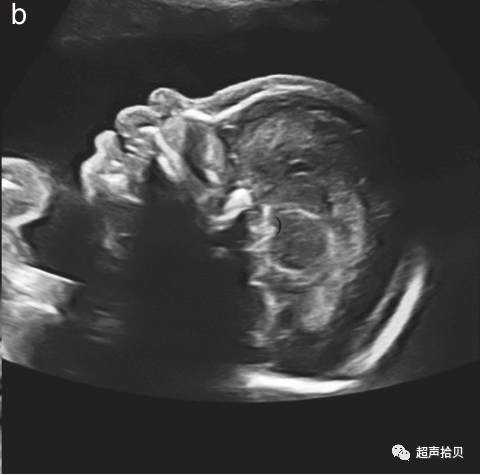

图2胎儿头部的横切面,显示标准的经脑室(a)、经小脑(b)和经丘脑(c)扫描平面。经脑室和经丘脑平面允许评估大脑半球区域的解剖完整性。经小脑平面允许评估后颅窝的小脑和大池(CM)。CP-脉络膜丛、CSP-透明隔腔、TH-丘脑。

大脑

用于胎儿大脑基本检查的标准扫描平面在更新的 ISUOG 指南20中有描述。两个横断面,通常称为经脑室平面和经丘脑平面,可以显示与大脑解剖完整性相关的大脑结构(图 2)。成像伪影掩盖了近端半球(更靠近探头的半球)。应添加第三个横断面-经小脑平面来评估后颅窝。应评估以下大脑结构:

• -侧脑室(包括脉络丛);